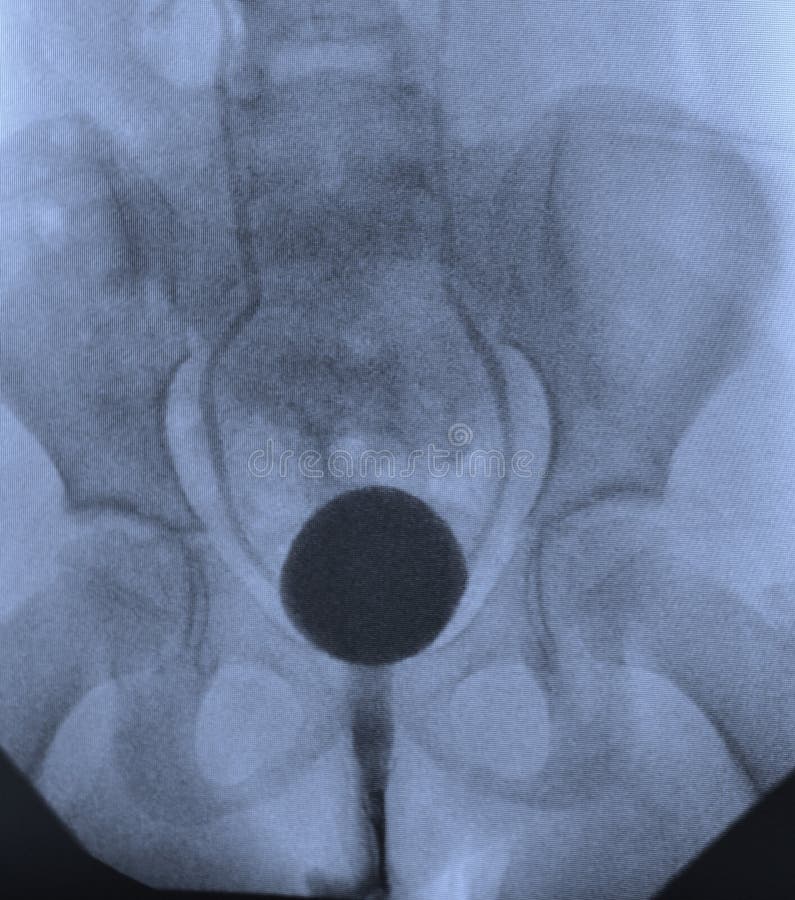

La dilatation est la méthode la plus ancienne de traitement du rétrécissement de l’urètre (cystoscopy bladder vescica vessie cistoscopia zystoskopie blaas blase cystoscope investigate prolapsus relatie baarmoeder anatomie). Cystoscopie vessie pleine ou vide. Un cathéter spécial est introduit dans l’urètre, ce qui permet de le dilater. Toutefois, l’effet de ce traitement ne dure pas longtemps, c’est pourquoi la dilatation doit être effectuée à plusieurs reprises.